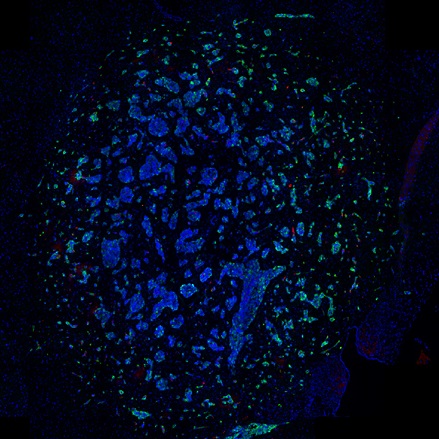

IF Tumor Vascularization

Segment tissue into tumor and stroma/healthy areas, detect CD31+ vessels, and quantify vessel number, area, density, and connectivity with configurable wall closing and distance linking.

vasculatization, cancer, stroma, tumor, blood vessels, CD31, spatial analysis, tumor microenvironment